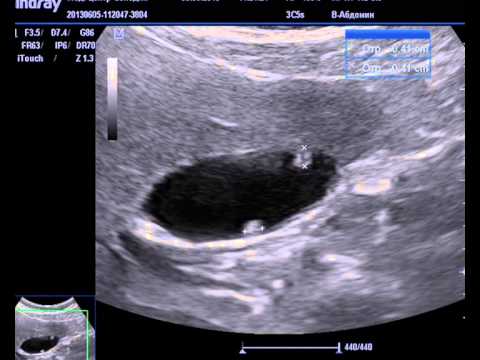

Как правило, на ранней стадии эта патология никак внешне себя не проявляет, и нередко обнаруживается случайно, в ходе процедуры ультразвукового обследования брюшной полости. Прежде, чем разобраться, опасны ли полипы в желчном пузыре при беременности, давайте разберемся, что это за болезнь.

Для данного заболевания характерно нарушение нормального течения в организме обменных процессов, что несет угрозу здоровью и матери, и будущего малыша. Поэтому, планируя беременность, необходимо обязательно пройти процедуру УЗИ органов брюшной полости на предмет наличия заболеваний этого резервуара для желчи.

Если обнаруженные новообразования не несут серьезной угрозы здоровью будущей матери, то врач может, не прибегая к операции, разрешить беременность. Однако в этом случае необходимы регулярные плановые осмотры с применением современных инструментальных методов диагностики, поскольку зачастую беременность провоцирует рост полипов.

Регулярно проходите ультразвуковое исследование для мониторинга состояния полипов. Это поможет своевременно выявить изменения и принять необходимые меры.